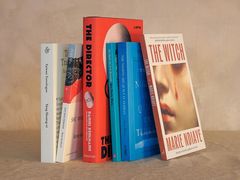

![[서울=뉴시스] 파운데이션 모델별 예측 성능 지표. (사진= 서울대병원 제공)](https://img1.newsis.com/2025/11/28/NISI20251128_0002005083_web.jpg?rnd=20251128094605)

[서울=뉴시스] 파운데이션 모델별 예측 성능 지표. (사진= 서울대병원 제공)

또 의료 영상 기반 모델이 항상 더 우수한 것은 아니며, 예측 성능이 높다고 해서 설명 가능성까지 함께 향상되는 것은 아니라는 점도 확인됐다. 이는 의료 AI가 실제 임상에서 활용되기 위해서는 정확도와 함께 ‘왜 그렇게 판단했는지’에 대한 근거 검증이 필수적임을 보여준다.